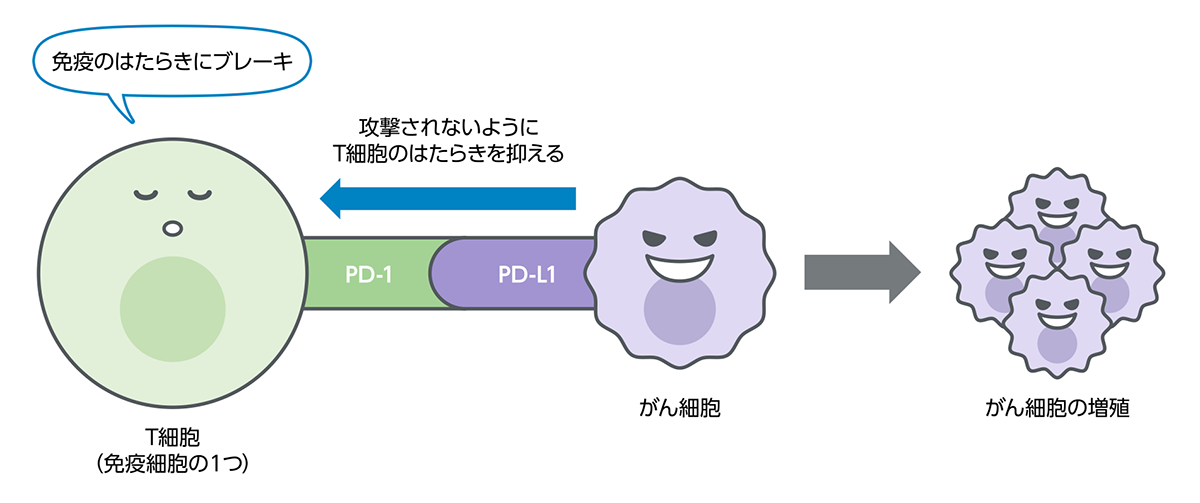

身わたしたちの身体には、体内に入り込んだ異物(自分の体の細胞ではないもの)を攻撃し、排除して体を守る「免疫」という働きが備わっています。

身体の中でがん細胞ができると、免疫の働きがそれを異物ととらえ、排除しようとします。

しかし、がん細胞は、免疫の攻撃から逃れるために、免疫細胞(T細胞など)にブレーキをかける力をもっています。このように、がん細胞によって免疫にブレーキがかけられた状態や、もともと免疫の働きが弱まった状態などでは、がん細胞を排除しきれないことがあります。

免疫の働きにブレーキをかける免疫チェックポイント

私たちの体には、細菌やウイルスなど外来の異物や、体の中でできたがん細胞などの異常な細胞の働きを抑えこみ、排除するための「免疫」という仕組みがあります。さらに免疫が過剰に働き、自分の体を攻撃しないように、免疫にブレーキをかける仕組みも備わっていることがわかってきました。がん細胞の中には、この仕組みを悪用し、免疫による排除から逃れているものもあります。

免疫の働きにブレーキをかける仕組みの1つが「免疫チェックポイント」と呼ばれる分子であり、「PD-1」はその1つです。「PD-L1」はPD-1と結合し、PD-1を活性化させる働きを持つ、細胞表面に存在するタンパク質です。がん細胞の中には、このPD-L1を細胞の表面に出すことによって、免疫の働きから逃れているものがあると考えられています。